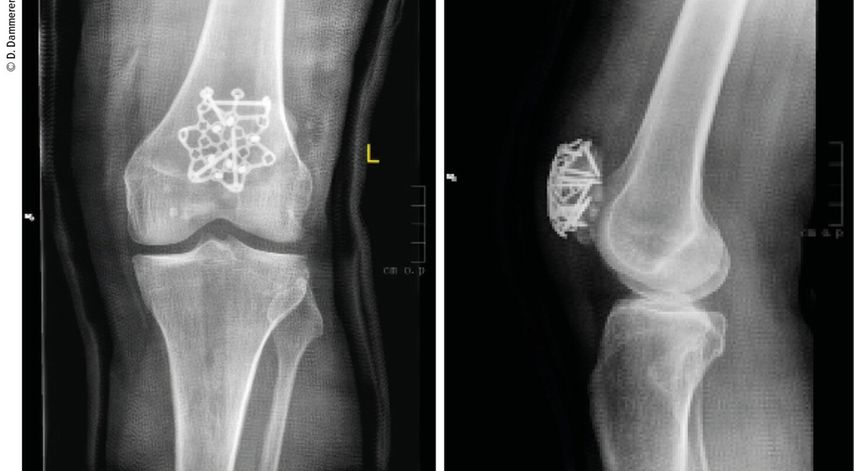

Abb. 2: Die operative Versorgung erfolgte mittels Sternplatte und zeigt ap und seitlich eine gute Reposition aller Frakturfragmente

Merkmale der Sternplatte

Es gibt verschiedene Plattendesigns für unterschiedliche Frakturformen:

-

einfache Frakturen: Sternplatte

komplexe Frakturen: Sternplatte mit 3-Loch- und 6-Loch-Erweiterung (= Beine), speziell zur Fixierung von distalen Fragmenten

Vorteile sind hier: Biegen und Anpassen der Sternplatte sind möglich, um die individuelle Anatomie zu berücksichtigen. Die Notwendigkeit einer Material-entfernung entfällt. Weichteilgewebe kann mit Nähten an der Sternplatte befestigt werden. Die Verriegelungslöcher haben variable Winkel, was eine Schraubenanwinklung von bis zu 15° ermöglicht, dadurch können selbst kleine Knochenfragmente erreicht werden. Für die Schraubenlöcher sind 2,7-mm-Verriegelungsschrauben und Kortikalschrauben geeignet. Die Verwendung von 2,4-mm-Verriegelungsschrauben kann in kleinen, nicht belasteten Arealen eingesetzt werden. Eine interfragmentäre Fixierung ist durch die zusätzlichen distalen Beine (3/6 Löcher) möglich.